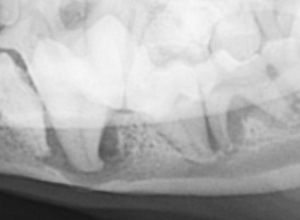

● 歯周病におけるレントゲンの撮影と読影法

中等度の歯周病におかされた歯のデジタルレントゲン撮影

( 無麻酔にて撮影 )

歯周病におかされた歯はほとんど支えている骨がないことに注目します。2番の左側の歯周病は1番の右側をおかしつつあり、2番の右側は3番の左側をおかしつつある。つまり諸悪の根源は、2番の歯であり、2番が1番の右側、3番の左側に影響してしまったという事がこの画像によって明確に理解できます。また赤く表現されている部分は歯石になります。歯の深部まで歯石が付着していることがわかります。当院では、骨残存率50%あれば、まずまずの改善。30%あれば、術後ケアによりより長い歯の寿命。20%以下では、ご家族に抜歯するか、なんとか残すかを伺う。そのような形をとっております。このレントゲン画像であれば、2番は抜歯を推奨し、その部位を縫合することで、1番と3番のこれ以上の歯周病の進行を停止し、1番と3番の寿命を延ばす。5番は歯周病が片側性に深部まで到達しているため、今後、きちんとしたケアができるかどうか? あるいはご家族が抜歯してケアを楽にしたいか、あるは残したいか。という判断にて治療方針を変更する形となります。